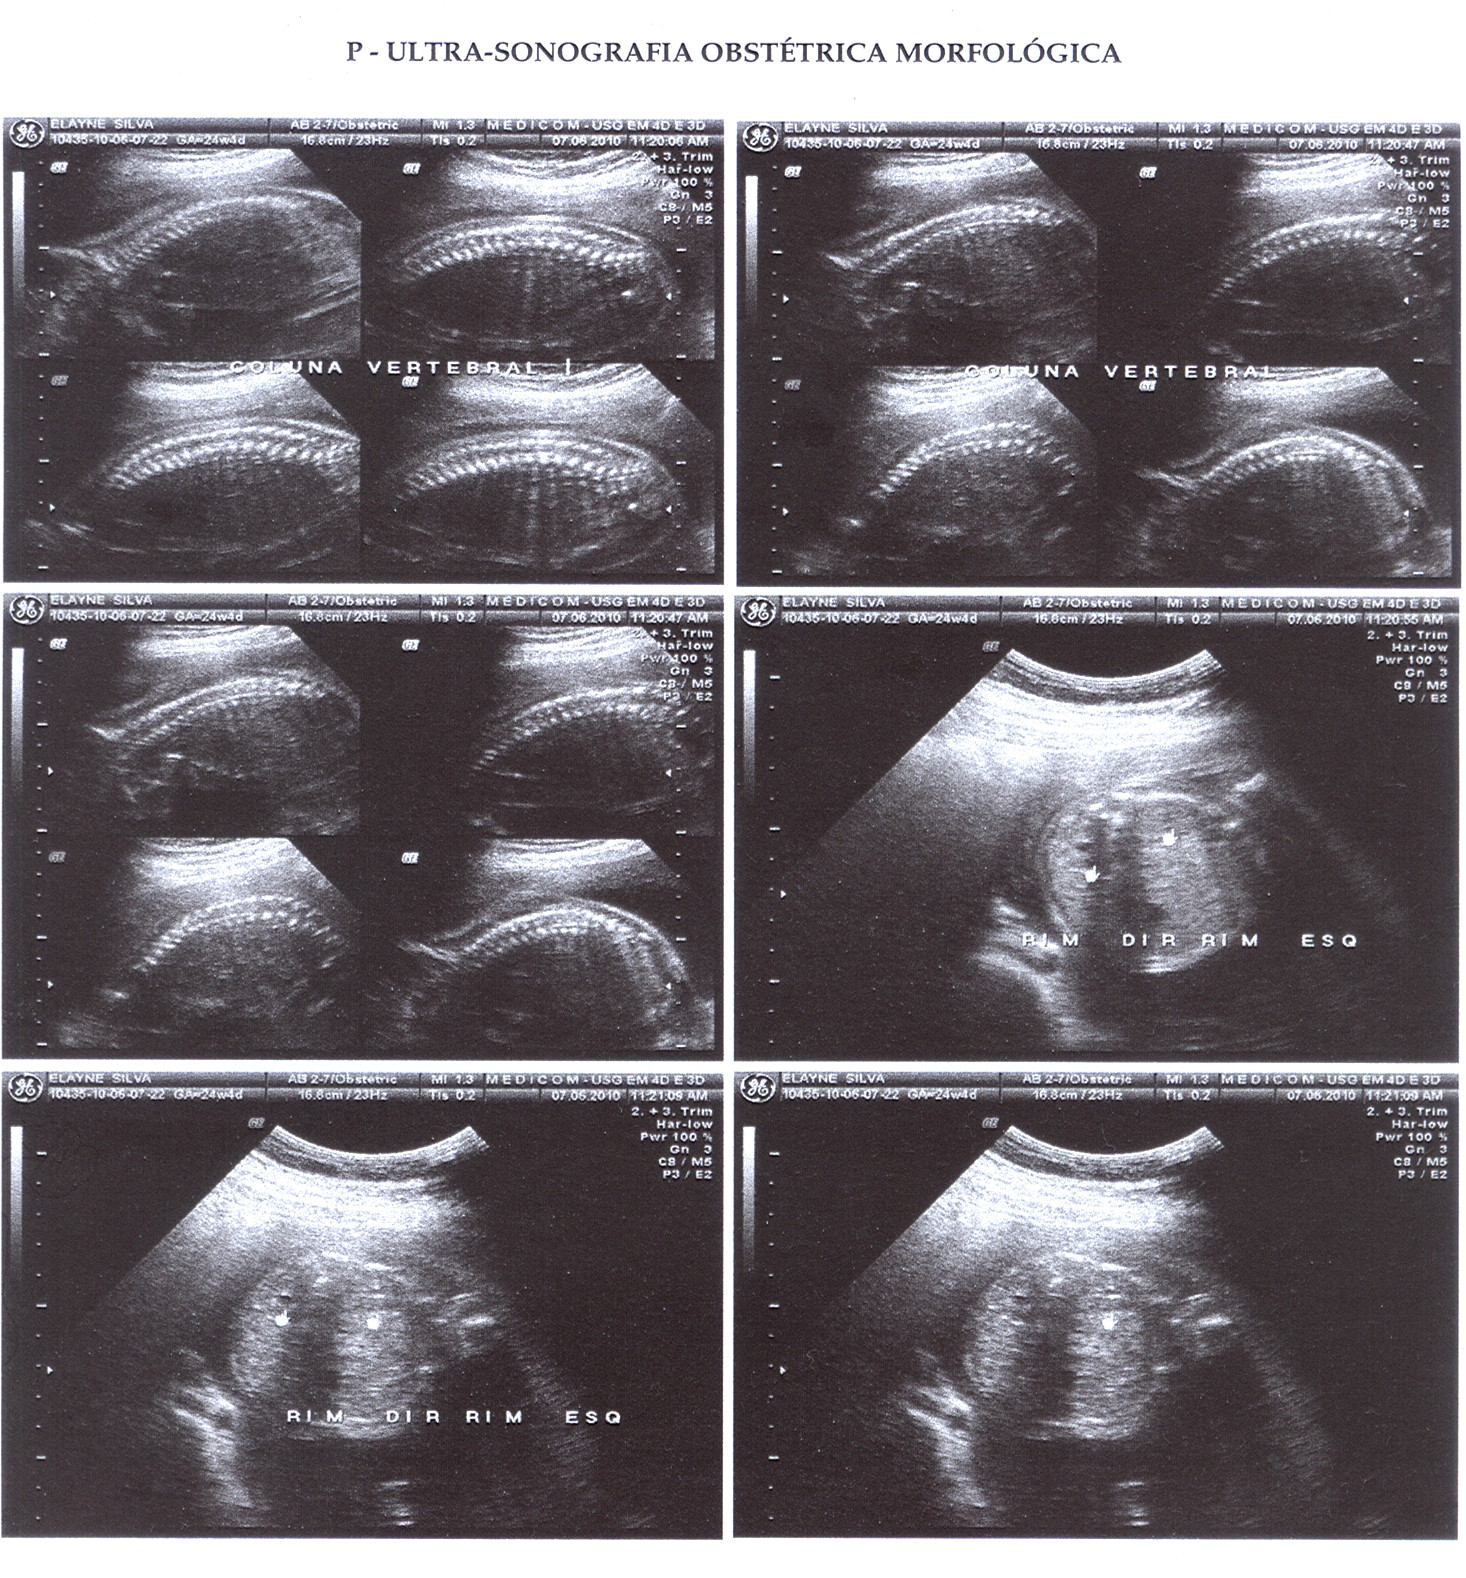

Situs Inversus Abdominalis. Feto en situação longitudinal, apresentação cefálica e dorso à direita.